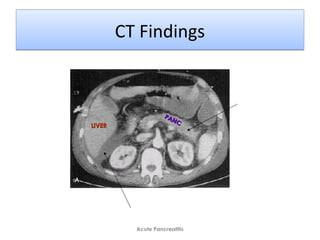

CT FindingsCT Findings

Tail Indistinct

Intraperitoneal fluid

PANC

LIVERLIVER

CT Findings

Severe Pancreatitis

• Pancreas

– Pancreatic enlargement

– Decreased density due to edema

– Intrapancreatic fluid collections

– Blurring of gland margins due to inflammation

• Peripancreatic

– Fluid collections and stranding densities

– Thickening of retroperitoneal fat